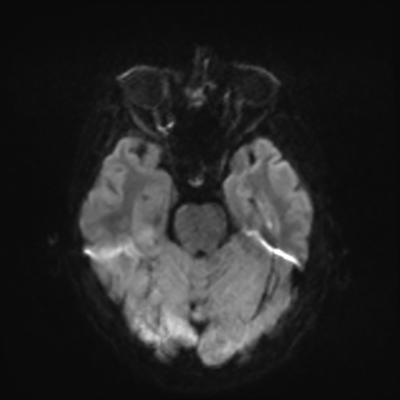

MRI brain (DWI)

You can clearly see diffuse cortical and basal ganglia diffusion restriction, and that of his deep cerebellar nuclei as well. The right occipital lobe abnormalities are a little more prominent, but then you remember that he is known to have had a right occipital stroke weeks ago.